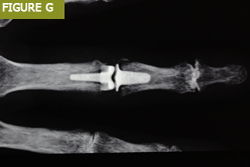

Parmak eklemi implantları için kullanılan malzemeler silikondan çeşitli sentetik plastik ve metal alaşımlarına kadar değişebilir (Şekil C). Kullanılan malzeme ve implant, ilgili eklem, hasta gereksinimleri ve mevcut cerrahi uzmanlık gibi çeşitli faktörlerle birlikte altta yatan patolojiye bağlıdır.

Parmak eklemi değiştirme implantları artık tüm parmak eklemleri için mevcuttur:

El bileği artroplastisinde çeşitli implant modülleri de kullanılmıştır: